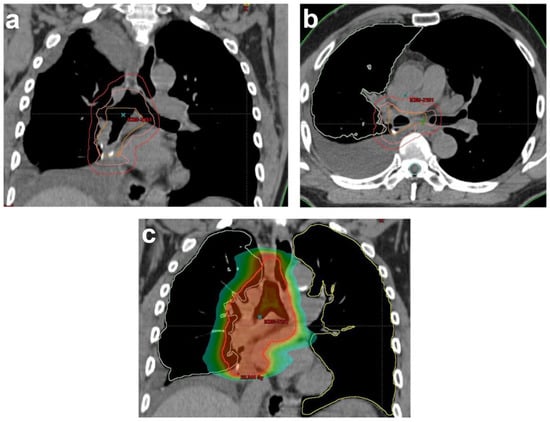

ESTRO/ACROP guidelines suggested that CTV should include the pathologically involved and resected mediastinal lymph node stations, bronchial stump, ipsilateral hilum and ipsilateral nodal stations 4 and 7. The definition of CTV depends on the lung lobe where the tumor was located, but the bronchial stump, ipsilateral hilum, positive lymph node regions and LN stations 4 and 7 must always be included in the CTV due to their high risk of relapse [83] (Figure 1).

Figure 1. Illustration of RT planning of PORT for a completely resected NSCLC patient with histologically proven lymph nodes (2/9) in stations 7 and 10R in (a) coronal and (b) sagittal views. Delineation based on the Lung ART protocol of rCTV (orange): bronchial stump, ipsilateral hilar node region (10R) and lymph node station 7. CTV (pink): rCTV+1 cm. In this case, 4R, 7 and 10R had a maximal upper limit to the top of the aortic arc and a maximal lower limit 5 cm below the carina. PTV (red); (c) color wash of dose distribution ranging from 20 Gy to 57.7 Gy (prescribed dose: 54 Gy). rCTV: resected clinical tumor volume, CTV: clinical tumor volume, PTV: planning target volume.